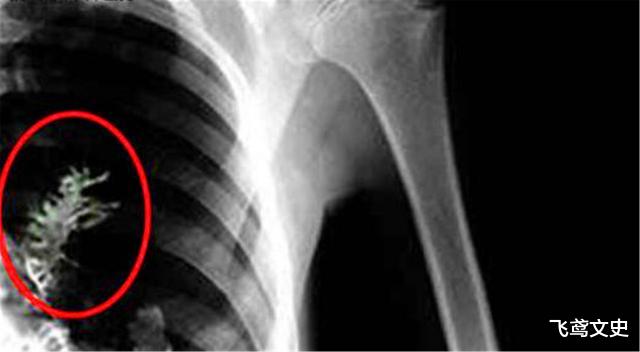

伤心的西多尔金并不愿意让家人也知道这个消息 , 因此选择了隐瞒 , 只能够独自一人来到医院进行手术 。 但是意外发生了 , 在给西多尔金进行手术的时候 , 医生被西多尔金身体内部的情况惊呆了 。 原来之前医生所发现的 , 里面并不是什么肿瘤 , 而是一颗正在茁壮生长的小树苗 。 跟被震惊住的医生不同的是 , 已经被麻醉的西多尔金并不知道发生了什么事情 。

最后经过了艰苦的努力 , 医生终于将这颗小树苗从西多尔金的身体里面取了出来 。 在取出来的过程中 , 医生发现这颗小树的茎叶已经是贯穿了西多尔金的身体的血管 , 这也是为什么西多尔金进行劳动较大的体力活动时 , 会觉得自己的呼吸困难 , 这是因为树苗的茎叶已经生长到了肺部里面去了 。 看着这颗小树苗 , 医生非常好奇到底是怎么生长到身体里面的 。